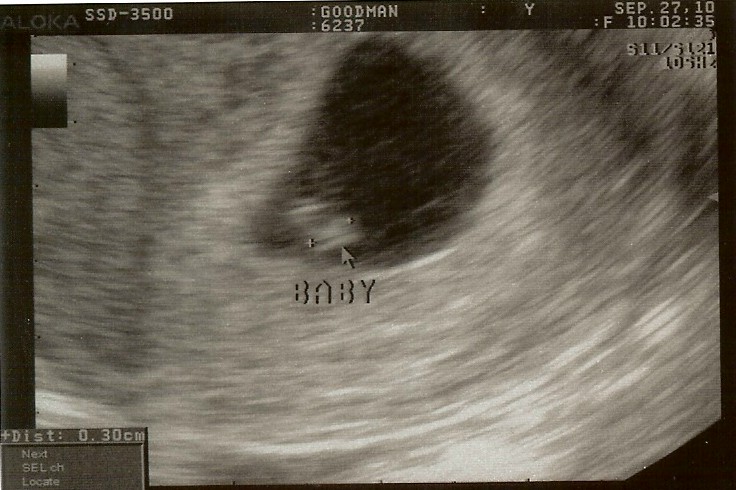

The ultrasound tech warned us that we shouldn’t be alarmed by silence because it probably too early to hear a heartbeat. When the TV turned on and the sound was working, all we could say was “Holy &*$@”. We heard a heartbeat even before we saw an image…Our baby was already ahead of his/her time. We couldn’t believe something was living inside of me. Hearing the heartbeat, however, was extremely convincing.

It was real…This was going to happen. The tech explained what we were looking at (which was basically a small, round beating image) and said the baby looked to be 6 weeks, 6 days. There was no head or fingers to make out. After we were finished, Greg and I starred at the ultrasound picture while we waited to meet with our doctor. I realized that Greg thought the huge black blog was the baby (which was really my uterus) and the white image was his/her heart. I couldn’t stop laughing, thinking how adorable he was (and thinking how much we both had to learn in the coming months).